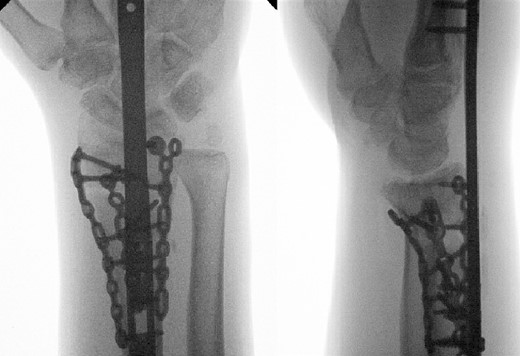

Two weeks following the procedure, the patient returned to the clinic for a follow-up visit. The wrist was swollen and ROM was limited. Hand motor functions and neurovascular exam were fully intact. Radiographs taken in clinic showed intact hardware with healing fracture. At 2 months follow-up, radiographs showed intact hardware with interval bone bridging across fracture sites. Radiographic parameters including articular alignment, radial height, radial inclination, and volar tilt were in acceptable ranges (Fig. 5). The patient reported no concerns or complications. A computed tomography (CT) scan was obtained at 10 weeks after the procedure and confirmed adequate bony healing and alignment without failure (Fig. 6). The dorsal spanning plate was eventually removed 1 month later and 4 months since the initial operation (Fig. 7).

Radiological assessment at 2 months postprocedure with PA and lateral views.

Dorsal spanning plate hardware removal at 4 months with a PA view.